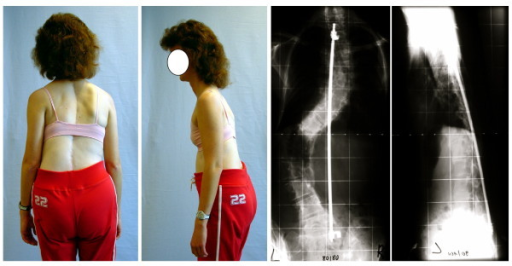

El objetivo de nuestro estudio fue analizar si la costoplastia es una opción válida para la corrección estética de la giba costal. Para esto, estudiamos una población homogénea con escoliosis idiopática del adolescente (EIA) con componente torácico, para evaluar el efecto de la costoplastia asociada a la artrodesis vertebral posterior instrumentada en la función pulmonar y la estética de los pacientes.

(2) SÁNCHEZ-MÁRQUEZ, J. M., et al. (2010): «Efecto de la costoplastia en la función pulmonar y la estética en pacientes con escoliosis idiopática del adolescente», Revista Española de Cirugía Ortopédica y Traumatología, vol. 54, n.o 3, 156-161.